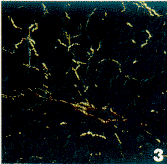

图3 3周模型组大鼠肝脏天狼猩红染色×200

Fig.3 Hepatic tissue was stained by sirius red-polarization in the model rat for 3 weeks ×200

1. 苦味酸-天狼猩红染色切片,偏振光显微镜下Ⅰ型胶原纤维呈强双折射为红色或黄色的粗纤维,Ⅲ型胶原呈弱双折射为绿色的细纤维。正常组和3周模型组肝脏汇管区和各级静脉周围有橘黄色的Ⅰ型胶原,在肝窦周有染成黄绿的、纤细的Ⅲ型胶原。5周模型组和7周模型组汇管区、中央静脉周围和窦周Ⅰ型胶原明显增多,染成亮红色。在5周组有不完整的纤维桥存在。7周组中央静脉之间和门管区之间形成了纤维索桥。成功建立了猪血清免疫大鼠肝纤维化模型(图1~3)。